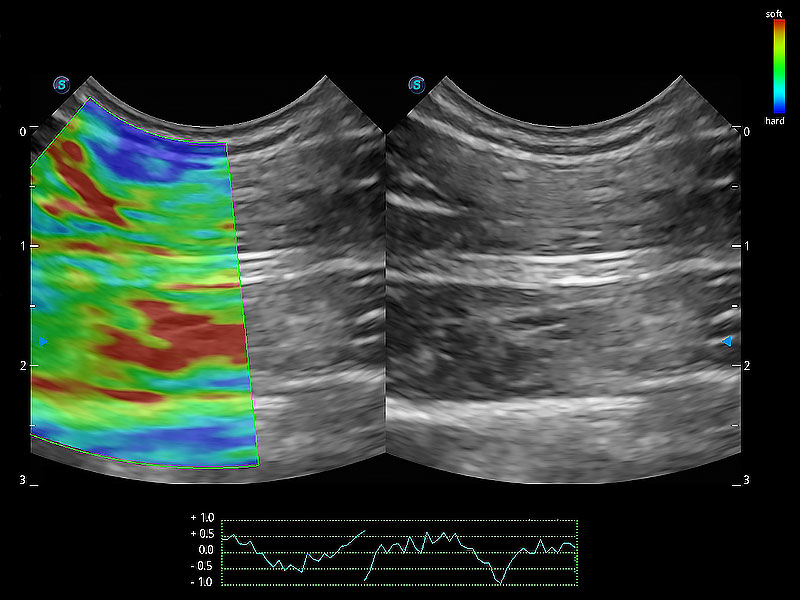

操作简便,无需高频度外力作用即可真实反映组织的形变,快速评估肿瘤良恶性。